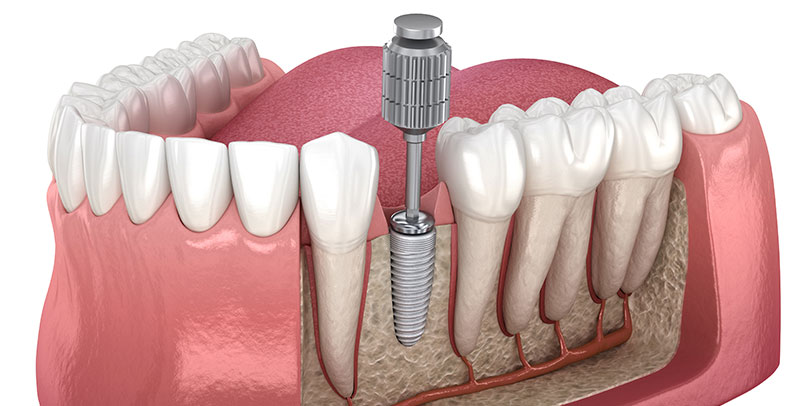

インプラント治療とは

インプラント治療とは、歯を失った部分の顎の骨に人工の歯根(インプラント体)を埋め込み、その上に人工の歯を装着して、歯の機能と見た目を回復する治療方法です。

天然の歯とほぼ同じ構造を再現できるため、義歯やブリッジよりもより良い見た目や噛み心地が得られます。

「自分の歯のように噛める治療」をご希望の方に、長期的な安定と快適性を両立する治療法としてお勧め致します。